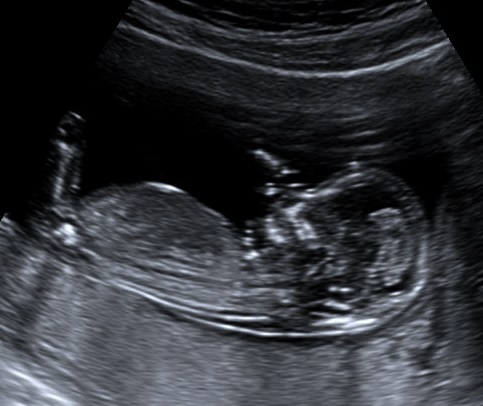

Attachment 19527Attachment 19528At my NT scan at 13 weeks (baby measured 14 weeks 1 day) the tech said if she had to bet she would say it is a girl. Yesterday I had a scan at 16 weeks(not sure where baby is measuring) with my ob he said he's not an expert but that he agrees with the tech that baby is a girl and that we can tell family just not announce on facebook(not a problem for me :) ). I'm still nervous that our little girl is actually a boy that's why I would love some more opinions/guesses from you all. Thanks!